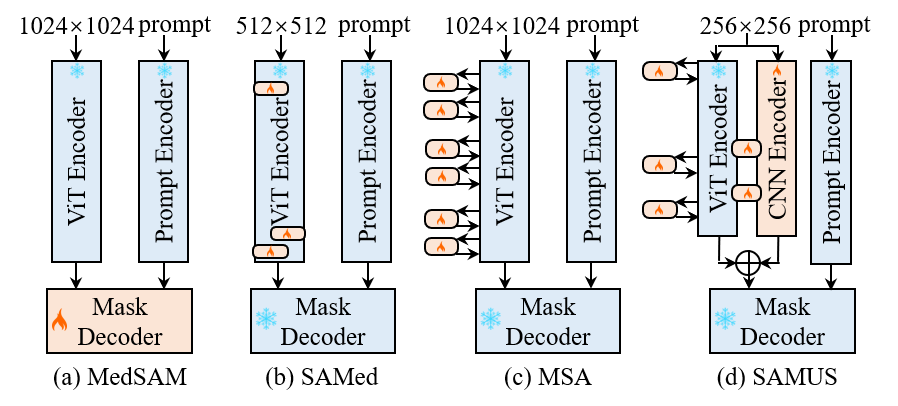

SAM has demonstrated remarkable performance in natural images but struggles with some medical image segmentation tasks, especially on objects with complex shapes, blurred boundaries, small sizes, or low contrast (Huang et al. 2023). To bridge this gap and enable SAM to adapt effectively to the medical image domain, several methods have been proposed to tune SAM using limited downstream medical datasets. MedSAM trains SAM on medical images at an acceptable cost by freezing the image encoder and the prompt encoder, focusing on tuning the mask decoder of SAM (Ma and Wang 2023). SAMed applies the low-rank-based (LoRA) strategy on the image encoder to tune SAM at a lower computational cost, making it more feasible for medical image segmentation (Zhang and Liu 2023). MSA adopts two down-ReLU-up adapters on each transformer layer of the ViT image encoder to introduce task-specific information (Wu et al. 2023). As illustrated in Fig. 1, compared to current SAM-based foundation models, the proposed SAMUS focuses more on complementing local features and reducing GPU consumption, which is crucial for accurate and easy-to-deploy medical image segmentation in clinical scenarios.